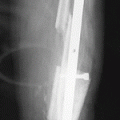

Additional supports for the femur at lower leg lengthening

The formation of persistent flexion stiffness of the knee joint that does not respond to conservative treatment can be a complication of lengthening of the lower leg. The lack of loading on the extremity can negatively affect the distraction regenerate; thus, the stiffness needs to be eliminated as soon as possible. For this purpose, a transosseous module is mounted on the femur as shown in Fig. 11.1a, or a ring support based on a wire and two half-pins is used (Fig. 11.3).